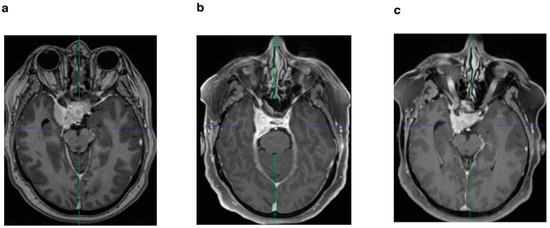

A microsurgical frontolateral approach was used to operate on all patients enrolled in this study at our institution. Due to the high morbidity associated with gross total resection of tumors infiltrating the cavernous sinus, surgical resection of the intracavernous portions was avoided. Intraoperative neuromonitoring of cranial nerves CN III, IV, V, and VI was performed in all surgeries. The extent of resection was determined on the basis of surgical reports and the Simpson grading scale at the 3 month follow-up MR imaging [16] and classified as follows: near-total resection (NTR), Figure 2a, in the case of a solely intracavernous residual tumor, and subtotal resection (STR), Figure 2a, in the case of intra- and extracavernous residual tumors.

Secondly, patients were divided on the basis of tumor resection. We identified 58 (61%) patients with near-total resection and 37 (39%) patients with subtotal resection (Table 1) (Figure 2a). A tumor recurrence was observed after near-total resection in nine (9.4%) patients. In contrast, 18 patients (18.9%) showed progression after subtotal resection. Both in the Kaplan–Meier analysis (p = 0.0011) (Figure 2b) and in the univariate (p ≤ 0.0018) and multivariate analysis (p ≤ 0.0001), the groups differed significantly (Table 2) (Figure 3).

Figure 2. (a) Diagram of enrolled medial sphenoid wing meningioma WHO grade I based on resection (NTR vs. STR); (b) Kaplan–Meier curve: PFS in relation to extent of resection (NTR vs. STR) in WHO grade I meningioma.